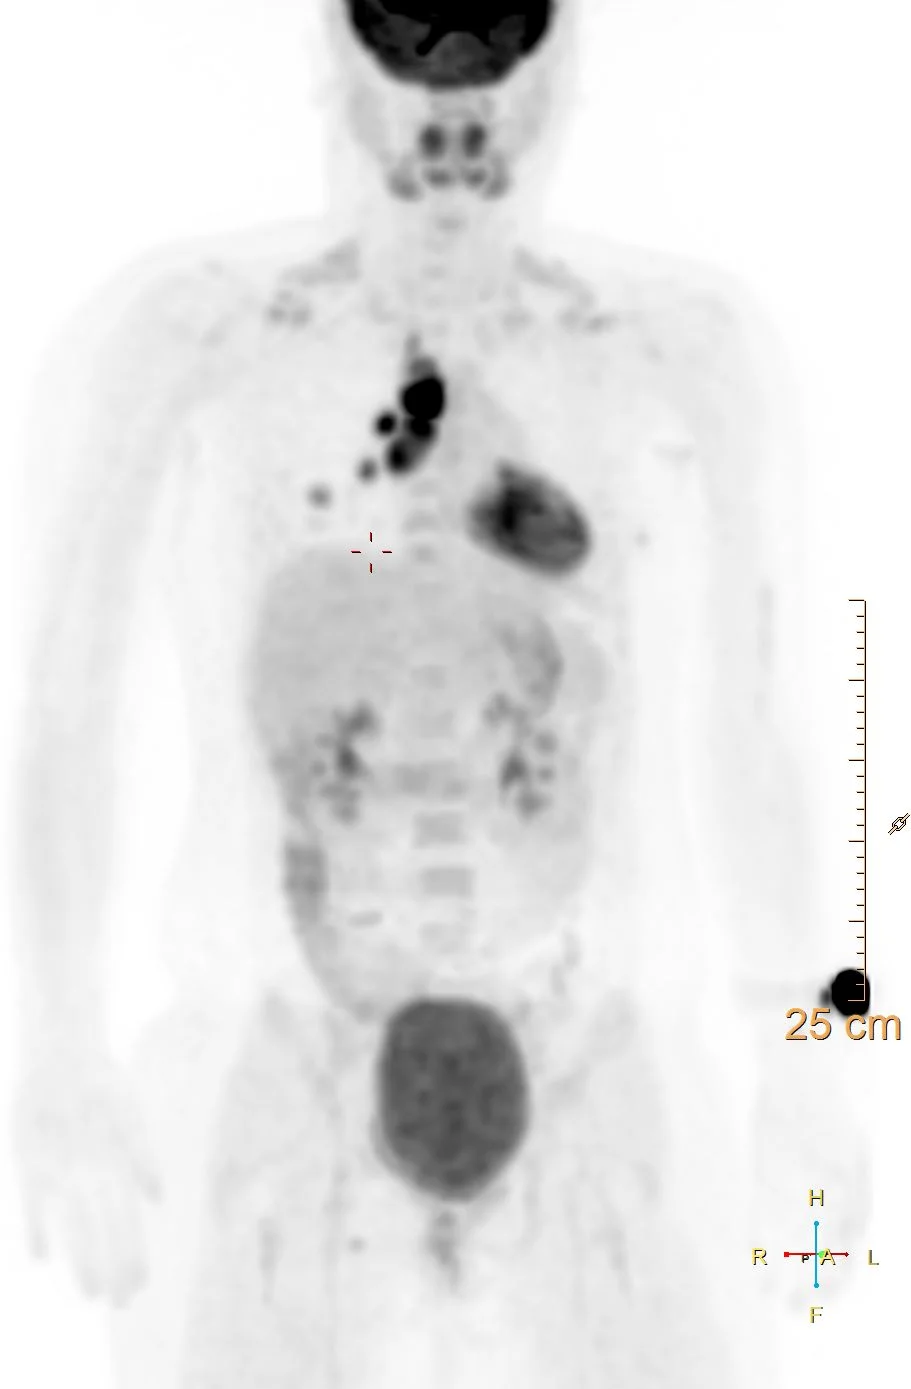

As malignancy was suspected, a PET scan was obtained, which shows marked FDG uptake in the lung opacity and lymph nodes. EUS guided FNA shows necrotizing granulomas, and serologic tests were consistent with histoplasmosis.

intense FDG uptake in mediastinal lymph nodes and lung opacity.